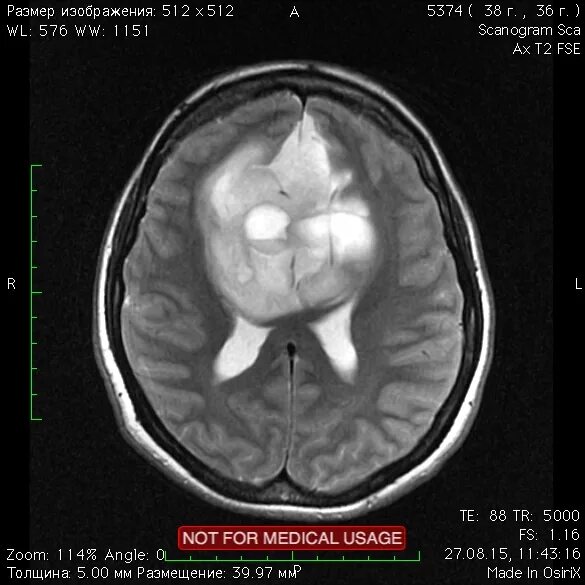

Астроцитома головного мозга прогноз после операции